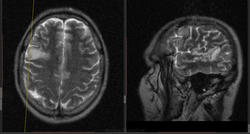

Мужчина 1959 года рождения, неделю назад почувствовал головную боль в правом виске, померил давление 170. Лечится около 5 дней сосудистыми препаратами, сейчас голова не болит, немного подтормаживает. Температура нормальная. Подскажите пожалуйста, о чем можно думать при такой картине?

Я так понимаю, очага два?  Дифференцировать с ишемическим НМК в подострой (судя по DWI) стадии. в клинике кроме головной боли и подтормаживания что-то есть?

Этот под подозрением. НМК в диф ряд принимается, сосуды справа "живее" левых, с чем дифференцировать? Вся известная клиника описана.

НМК, нейроинфекция?

Ишемический инсульт, подостр стадия.